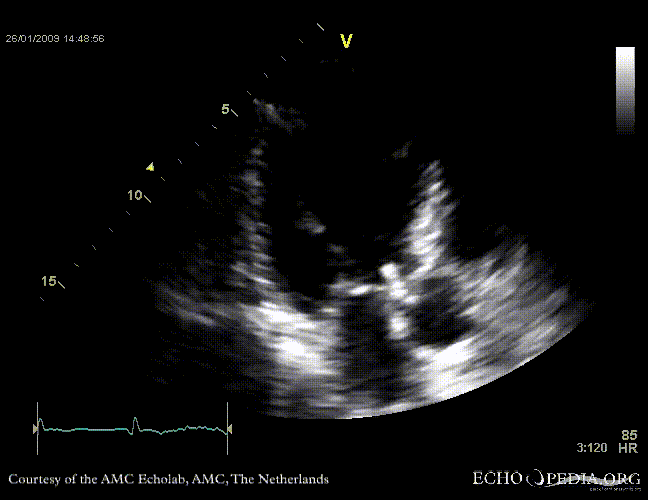

Aortic valve endocarditis with vegetation

Case description: This patient had endocarditis with an aortic valve vegetation

PLAX aortic valve vegetation A3CH aortic valve vegetation